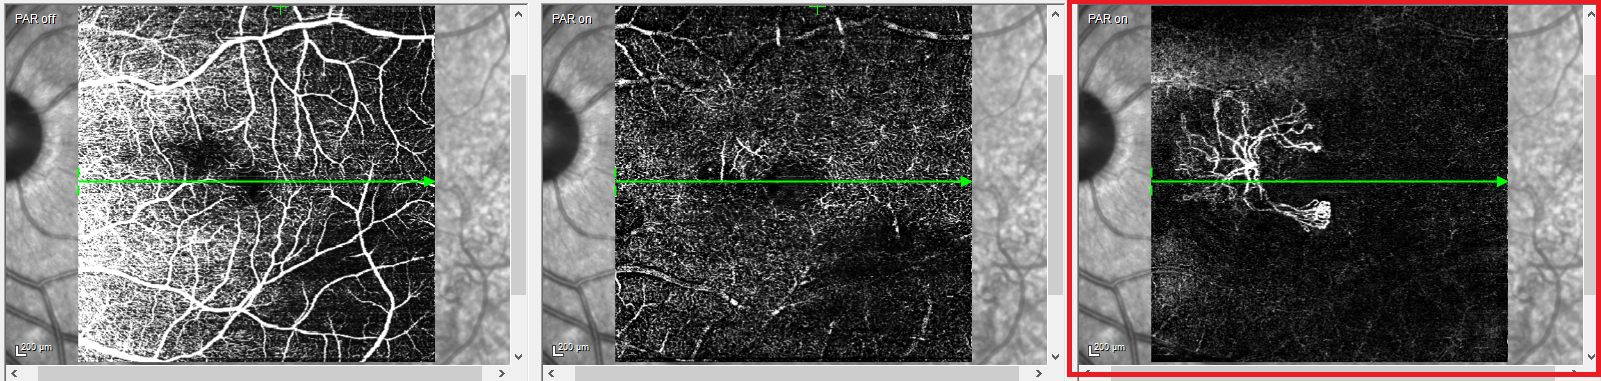

This is the radial scan pattern of MS-39 versus the radial scan pattern of ANTERION.

Metrics APP numbers of radial scans

What is 6 radial scans

Corneal data is derived from 65 radial cuts scanned across the cornea and this measured diameter.

Bonus - This is the total number of data points revealed by the 65 radial cut scan pattern.

Bonus - What are 16,640 data points?